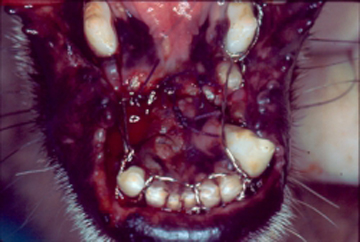

Los problemas que aquejan los tejidos periodontales son varios aunque su etiología primaria siempre es la misma, el alimento y las bacterias que se pegan a los dientes formando la placa dento bacteriana (PDB) y el sarro que destruyen lentamente pero de manera progresiva los tejidos de sostén dental. La enfermedad periodontal es la enfermedad de mayor incidencia y prevalencia en perros y gatos por lo que su diagnóstico, prevención y tratamiento es uno de los retos que el médico veterinario tiene en su trabajo clínico. La enfermedad periodontal es la causa más común de enfermedades como endocarditis bacteriana y artritis infecciosa por lo que el propietario y médico tratante deben de tener especial interés en la prevención y tratamiento de esta patología. La enfermedad periodontal se clasifica dependiendo de los tejidos afectados así como según el grado de destrucción del tejido óseo. Según el tejido afectado como “Gingivitis” cuando afecta la encía libre y papilar, y “Periodontitis” cuando ya afecta el tejido óseo y el ligamento periodontal formando destrucciones del hueso alveolar muy características de la enfermedad denominadas bolsas periodontales las cuales según la forma de destrucción pueden clasificarse como horizontales o verticales. La periodontitis se diagnóstica con una sonda periodontal que es un instrumento que tiene líneas de medición en su punta de trabajo y que se introduce en el surco gingival para medir en milímetros la destrucción ósea alveolar. Otro método de diagnóstico es la radiografía periapical en la cual se puede observar claramente el grado y forma de destrucción ósea alveolar.

Haz CLICK sobre la imagen para ver descripción.